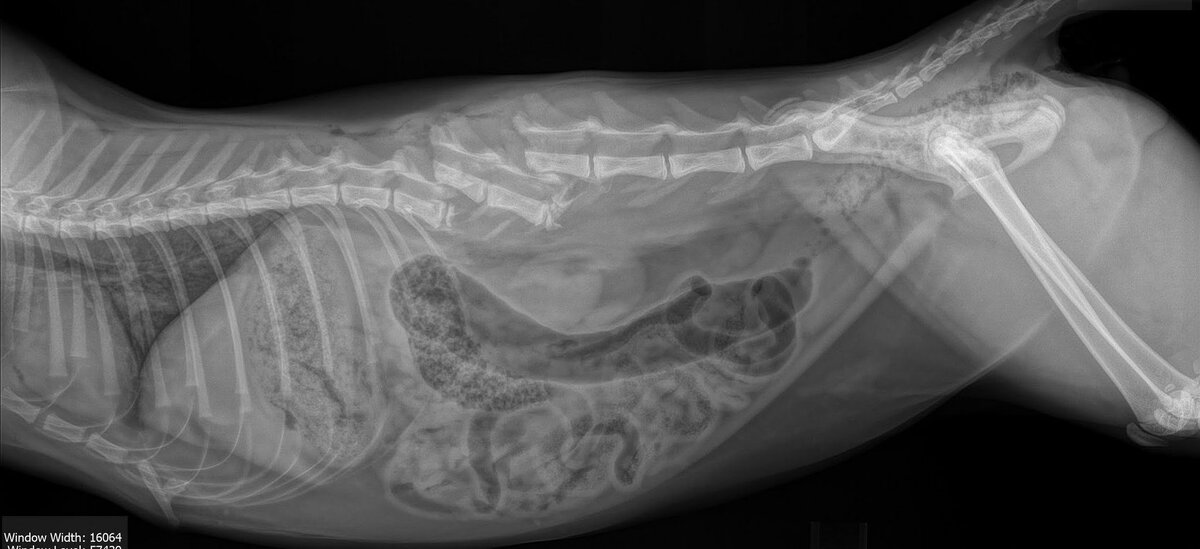

Частые последствия: 3. Ушибы, разрывы внутренних органов: ⠀

3. Ушибы, разрывы внутренних органов:

• мочевого пузыря;

• легких;

• печени и селезенки;

• диафрагмы;

• почек и др. ⠀

Частые последствия:⠀

• мочевой перитонит; ⠀

• отравление азотистыми веществами;

• пневмоторакс (воздух в грудной полости);

• внутреннее кровотечение;

• перемещение органов из брюшной полости в грудную;

• нарушение работы органов и др.

Важно максимально быстро доставить кошку в хорошую клинику, где возможна реанимация и диагностика: есть рентген, УЗИ, кислородная камера для противошоковой терапии. ⠀

За фото благодарим ветврачей из клиника

"Эпиона" и ветврача Михаила Шелякова